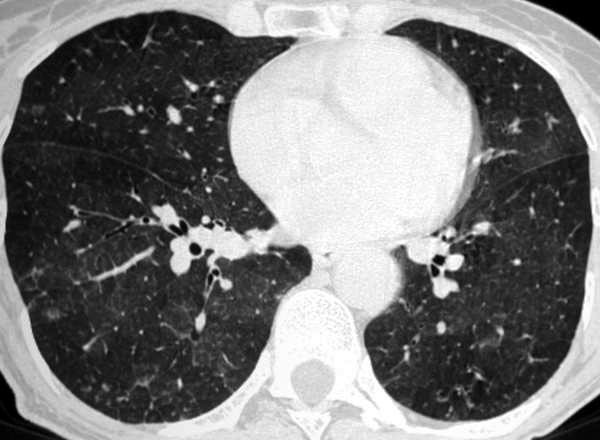

Eleveur d’oiseau. lésion élémentaire? Diagnostic?

Nodules de contours flous. pneumopathie d’hypersensibilité